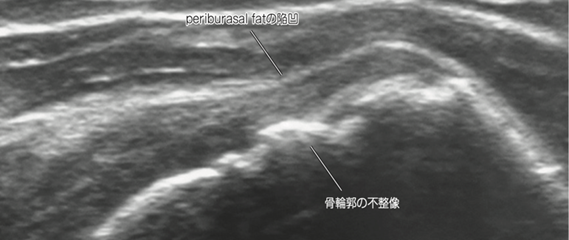

【特集】超音波(エコー)で見る、あなたの身体の中 -診断から最新治療まで-

近年、整形外科領域において超音波(エコー)検査は、腱板断裂の診断と「治療」において非常に重要な役割を担っています。

リアルタイム観察

エコーは、肩を動かしながら腱板の状態をリアルタイムで観察できるため、動的な病態評価が可能です。これにより、腱板の断裂部位や断裂の程度、周囲組織との関係性をより正確に把握できます。

エコー検査では、腱板の連続性の途絶や、腱の肥厚・菲薄化、炎症の有無などを確認します。これにより、腱板断裂の診断だけでなく、腱板炎や石灰性腱炎など、他の肩の疾患との鑑別も行います。

出典:西頭知宏, 笹沼秀幸, 飯島裕生, & 竹下克志. (2023). 関節の超音波所見. 臨床画像, 39(1), 18-25.